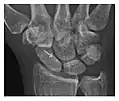

High-energy trauma fractures

Occult osseous injuries may result from a direct blow to the bone by compressive forces of adjacent bones against one another or by traction forces during an avulsion injury. Lesions in the tibial plateau, hip, ankle, and wrist are often missed. In a tibial plateau fracture, any disruption of the posterior and anterior cortical rims of the plateau should be sought. Impaction of subchondral bone will appear as an increased sclerosis of the subchondral bone (Figure 1). In the hip, posterior acetabular fractures also present subtle radiographic findings. The acetabular lines should then be carefully examined keeping in mind that the posterior rim, which is harder to see on X-rays, is more frequently fractured than the anterior rim (Figure 2). In the wrist, detection of carpal bone fractures is often challenging, with up to 18% of scaphoid fractures radiographically occult. Carpal fractures, especially the scaphoid, are associated with the risk of avascular necrosis. In apparently normal wrist radiographs from symptomatic patients, if there is history of a fall on an outstretched hand with pain in the anatomic snuffbox, suggesting scaphoid injury, the initial examination with posteroanterior, lateral, and pronation oblique views must be complemented by other specific views such as supination oblique and the "scaphoid" view A careful examination of cortices for evidence of discontinuity or offset and cancellous bone for lucency is necessary (Figure 3).[1]

Figure 3: A 26-year-old man presenting with wrist pain after being assaulted. (a) Initial anteroposterior radiograph shows a subtle linear lucency within the scaphoid extending to the scaphocapitate articular surface that was overlooked (arrow). (b) Initial "scaphoid" view was negative. (c) Followup anteroposterior radiographs, 12 days later, shows obvious scaphoid fracture (arrows).[1]

Triquetral fracture usually occurs on the dorsal aspect by impingement from the ulnar styloid or avulsion of strong ligamentous attachment. The dorsal avulsion fracture or "chip fracture" appears as a small bony fragment on the dorsal aspect of the triquetrum and is best detected on the lateral view(Figure 4). When radiography is negative in patients with high suspicion of a fracture, both MRI and MDCT will be of value. However, it has been shown that MRI is superior for detecting trabecular fractures in carpal bones.

-

a -

b

Figure 4: Dorsal triquetral fracture of the left wrist in a 30-year-old man after a trauma. (a) Anteroposterior radiograph shows a normal appearance. (b) Lateral radiograph of the same wrist demonstrates a chip fracture off the dorsal aspect of the triquetrum (arrow).[1]